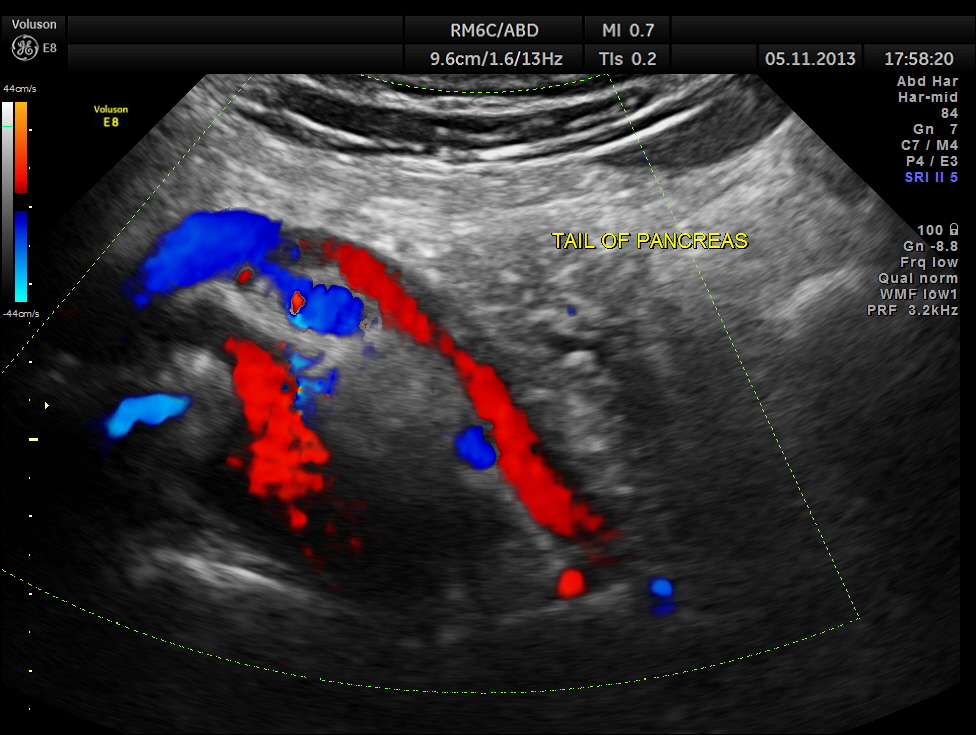

Part of the body and the tail of the pancreas seen.